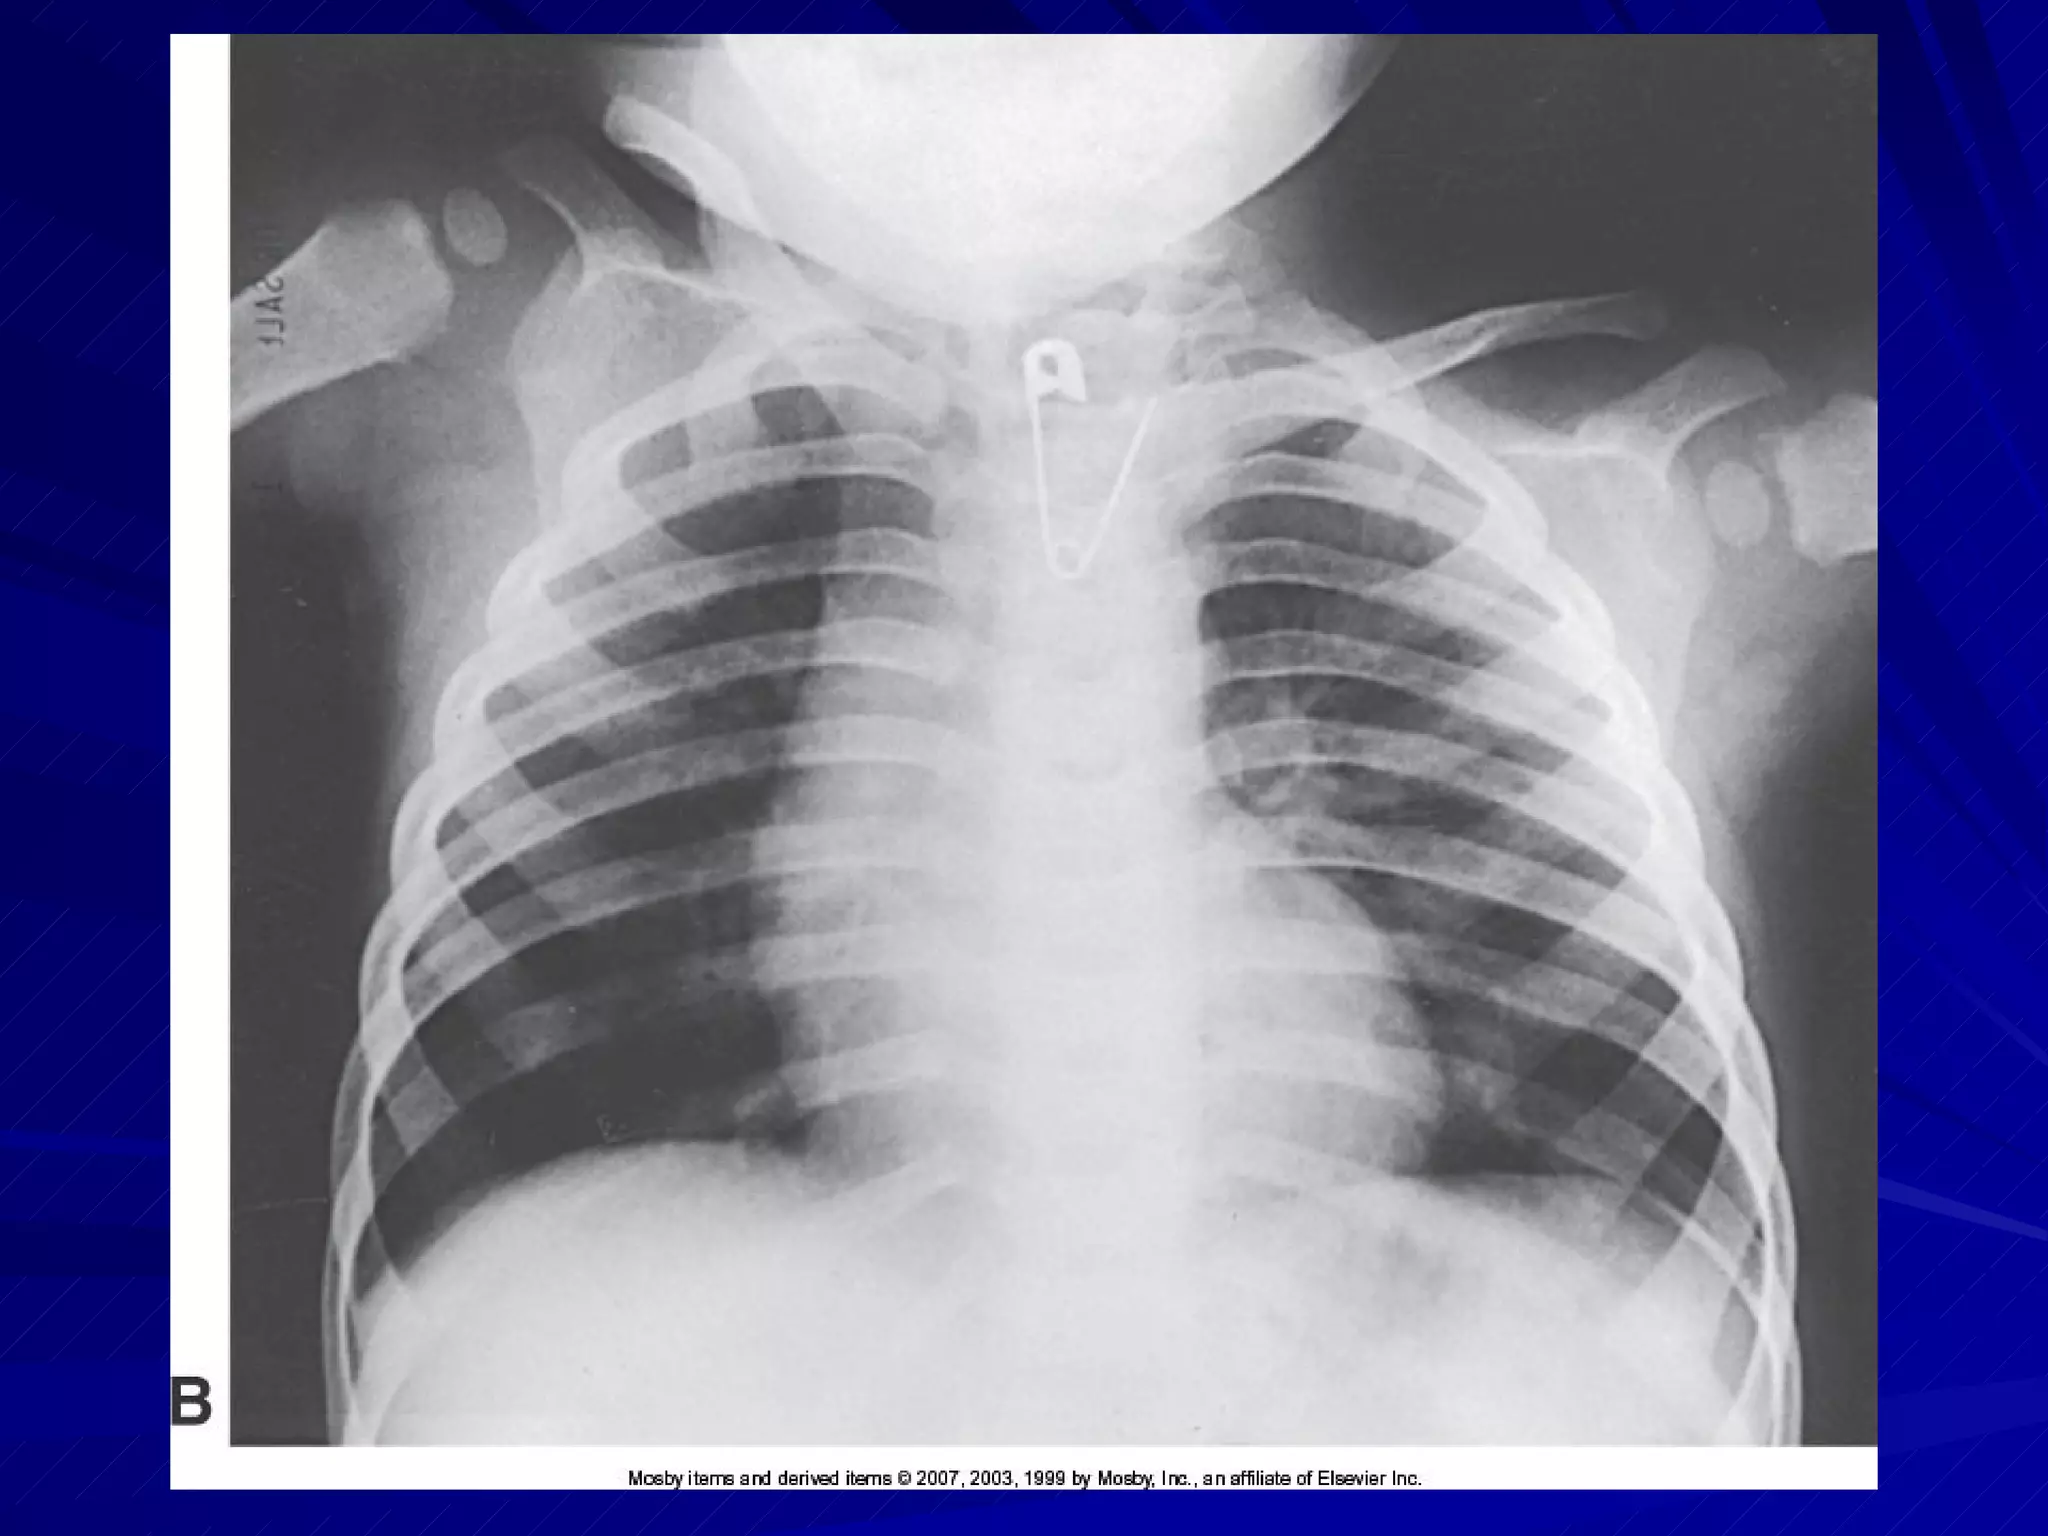

Chest Supine position used if general survey image of chest desired Check for need to demonstrate air-fluid levels If air-fluid levels are suspected, use X-table lateral If patient’s condition permits, lateral decubitus position with patient lying on affected side will also show air-fluid levels

Trauma AP Chest Obtain help to lift patient for IR placement Top of IR placed about 1.5   to 2   above shoulders Arms abducted MCP parallel to IR Use maximum SID to reduce heart magnification

Trauma AP Chest Ensure chin extended out of anatomy of interest CR directed perpendicular to center of IR look for light field slightly above shoulders and on sides of chest, CW or LW Exposure made upon second full inhalation, if possible

Trauma AP Chest Image demonstrates lung fields in their entirety Minimal rotation and distortion present

Chest Supine positionused if general survey image of chest desired Check for need to demonstrate air-fluid levels If air-fluid levels are suspected, use X-table lateral If patient’s condition permits, lateral decubitus position with patient lying on affected side will also show air-fluid levels

Trauma AP ChestObtain help to lift patient for IR placement Top of IR placed about 1.5  to 2  above shoulders Arms abducted MCP parallel to IR Use maximum SID to reduce heart magnification

Trauma AP ChestEnsure chin extended out of anatomy of interest CR directed perpendicular to center of IR look for light field slightly above shoulders and on sides of chest, CW or LW Exposure made upon second full inhalation, if possible

Trauma AP ChestImage demonstrates lung fields in their entirety Minimal rotation and distortion present